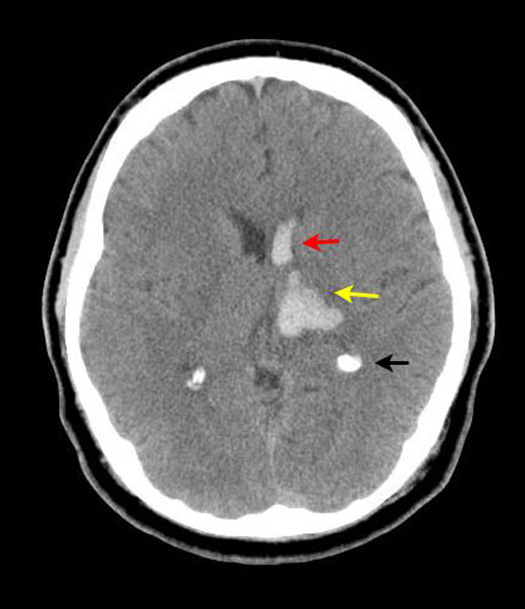

Figure 2: Non-contrast axial CT head

|

Hypertensive Hemorrhagic Infarct

Case 2:

Imaging findings: Figure 2

-

Hemorrhage (hyperdense area) involving left basal ganglia/thalamic regions (yellow arrow) is noted.

-

Extension of hemorrhage into left frontal horn (red arrow).

-

Black arrow points to normal calcification of choroid plexus.

Hemorrhage secondary to hypertension is more common in basal ganglia / thalamic regions.

Not a candidate for thrombolytic therapy or anticoagulation. |